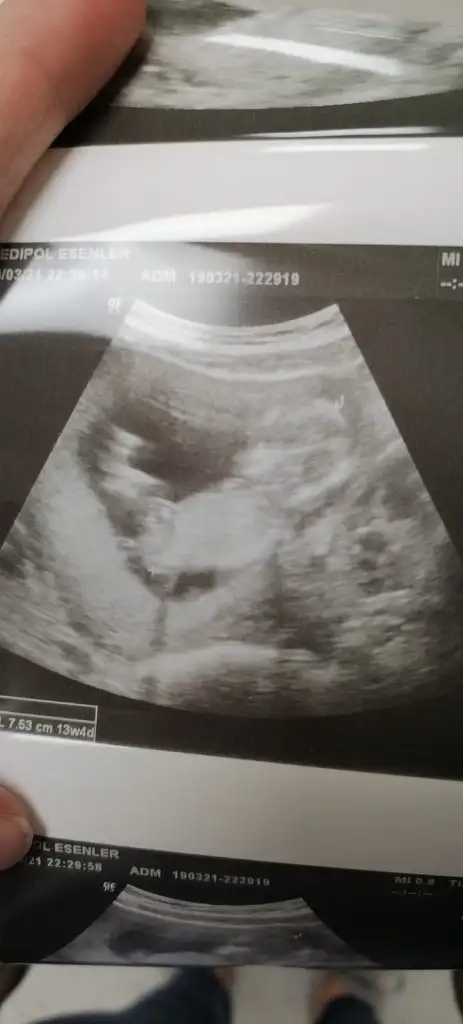

Skull teorisi ne göre yaparsin diye atmistimBaşı var bebeğin nubu görünmüyor

Nub gördümmu paylastinmi 11 12 13 haftalar kafaya göre kızSkull teorisi ne göre yaparsin diye atmistim

Coguda kafaya görr erkek diyo bende kiz hissediyorum nub bu var sirf bak bakalmNub gördümmu paylastinmi 11 12 13 haftalar kafaya göre kız

Buna göre ne diyosunCoguda kafaya görr erkek diyo bende kiz hissediyorum nub bu var sirf bak bakalm

Kız canim kafa için bak resim attimCoguda kafaya görr erkek diyo bende kiz hissediyorum nub bu var sirf bak bakalm

Coguda kafaya görr erkek diyo bende kiz hissediyorum nub bu var sirf bak bakalm

Ama benimkinin kafasi köseli degilmi yusyuvarlak degil sankiKız canim kafa için bak resim attimEki Görüntüle 2804795